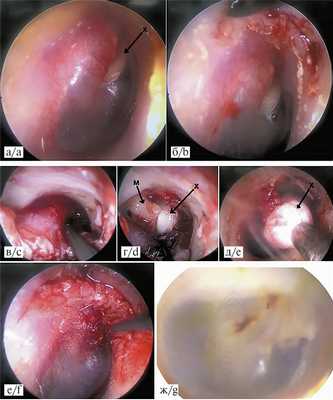

Холестеатома у детей с тимпанальной ее локализацией в 21 случае удалялась трансканально эндоскопически, в 19 — под контролем микроскопа заушным доступом (контрольная подгруппа). После тимпанотомии выполнялось удаление холестеатомы (см. рисунок на цв. вклейке), при необходимости — аттикотомия либо адито-аттикотомия. В случае наличия перфорации барабанной перепонки материалом для пластики также служили хрящ и надхрящница козелка либо фасция височной мышцы.

Этапы трансканального эндоскопического удаления тимпанальной холестеатомы: отоскопическая картина до операции (а), дугообразный разрез кожи НСП (б), отсепаровка меато-тимпанального лоскута (в), тимпанотомия (г), удаление тимпанальной холестеатомы (д), завершение операции (е), отоскопическая картина через 6 мес после операции (ж).

М — молоточек, х — холестеатома.